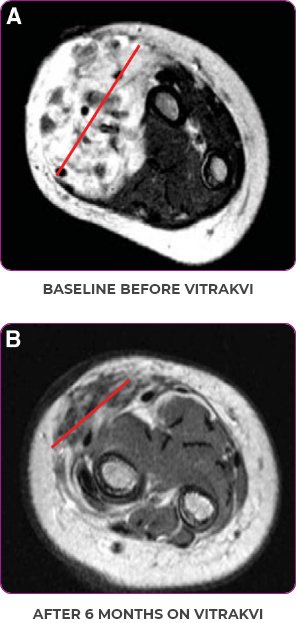

BASELINE BEFORE VITRAKVI

AFTER 6 MONTHS ON VITRAKVI

PATIENT CASE:

INFANTILE FIBROSARCOMA

OF SOFT TISSUE1

- 5-month-old with IFSa

- Progression after chemotherapy

- Confirmed PRa after 4 cycles of VITRAKVI® (larotrectinib)

- Referred for definitive limb-sparing surgery after 6 cycles

of VITRAKVI; achieved pCRa,b

Response to VITRAKVI1

- Patient achieved a confirmed partial response after 4 cycles of VITRAKVI with a 45% reduction in tumor burden

- Following 6 cycles of VITRAKVI, the patient was referred for definitive limb-sparing surgery

- Pathology revealed a complete pathologic response and clear resection margins with scar tissue noted

Reduction in tumor burden1

MRIa imagery of the brain. Red line indicates the maximum dimension.1

aMRI, magnetic resonance imaging.

Pre- and post-treatment imaging, by DuBois SG et al, is licensed under CC BY 4.0.